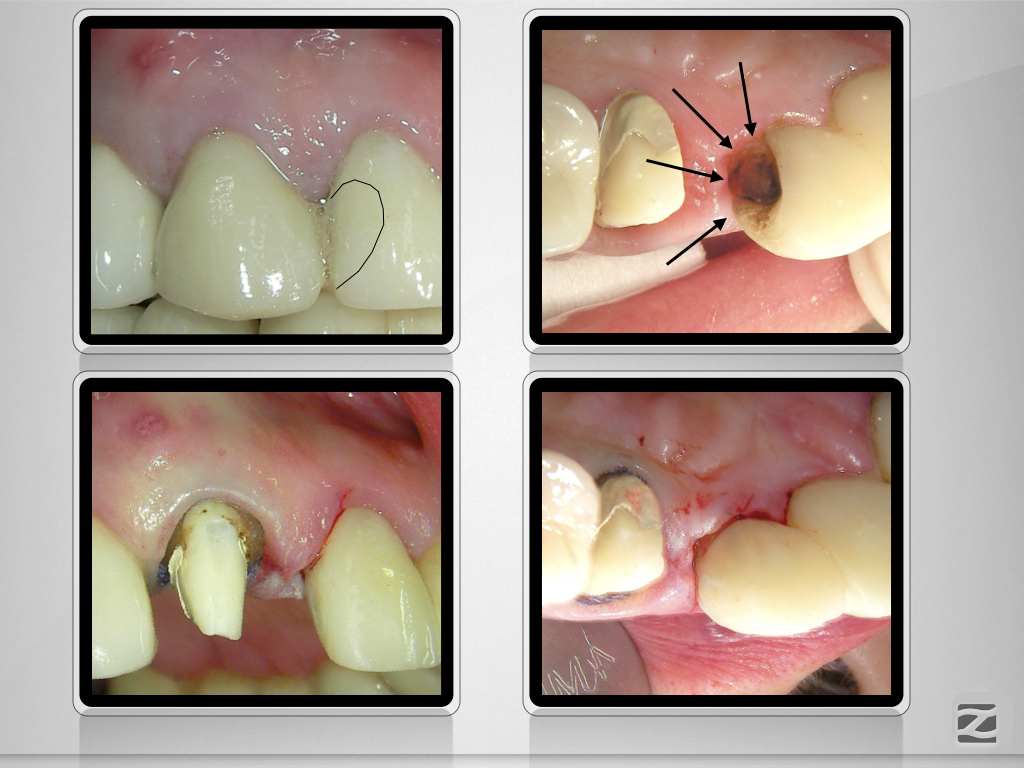

Laterale Perforation